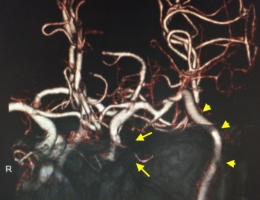

治療後

物が二重に見えるようになって発症した内頚動脈大型動脈瘤(矢印)の症例です。クリッピング術で直接動脈瘤をつぶすことができないため、バイパス術(矢印)を増設し内頚動脈を遮断することで動脈瘤を治療しました。